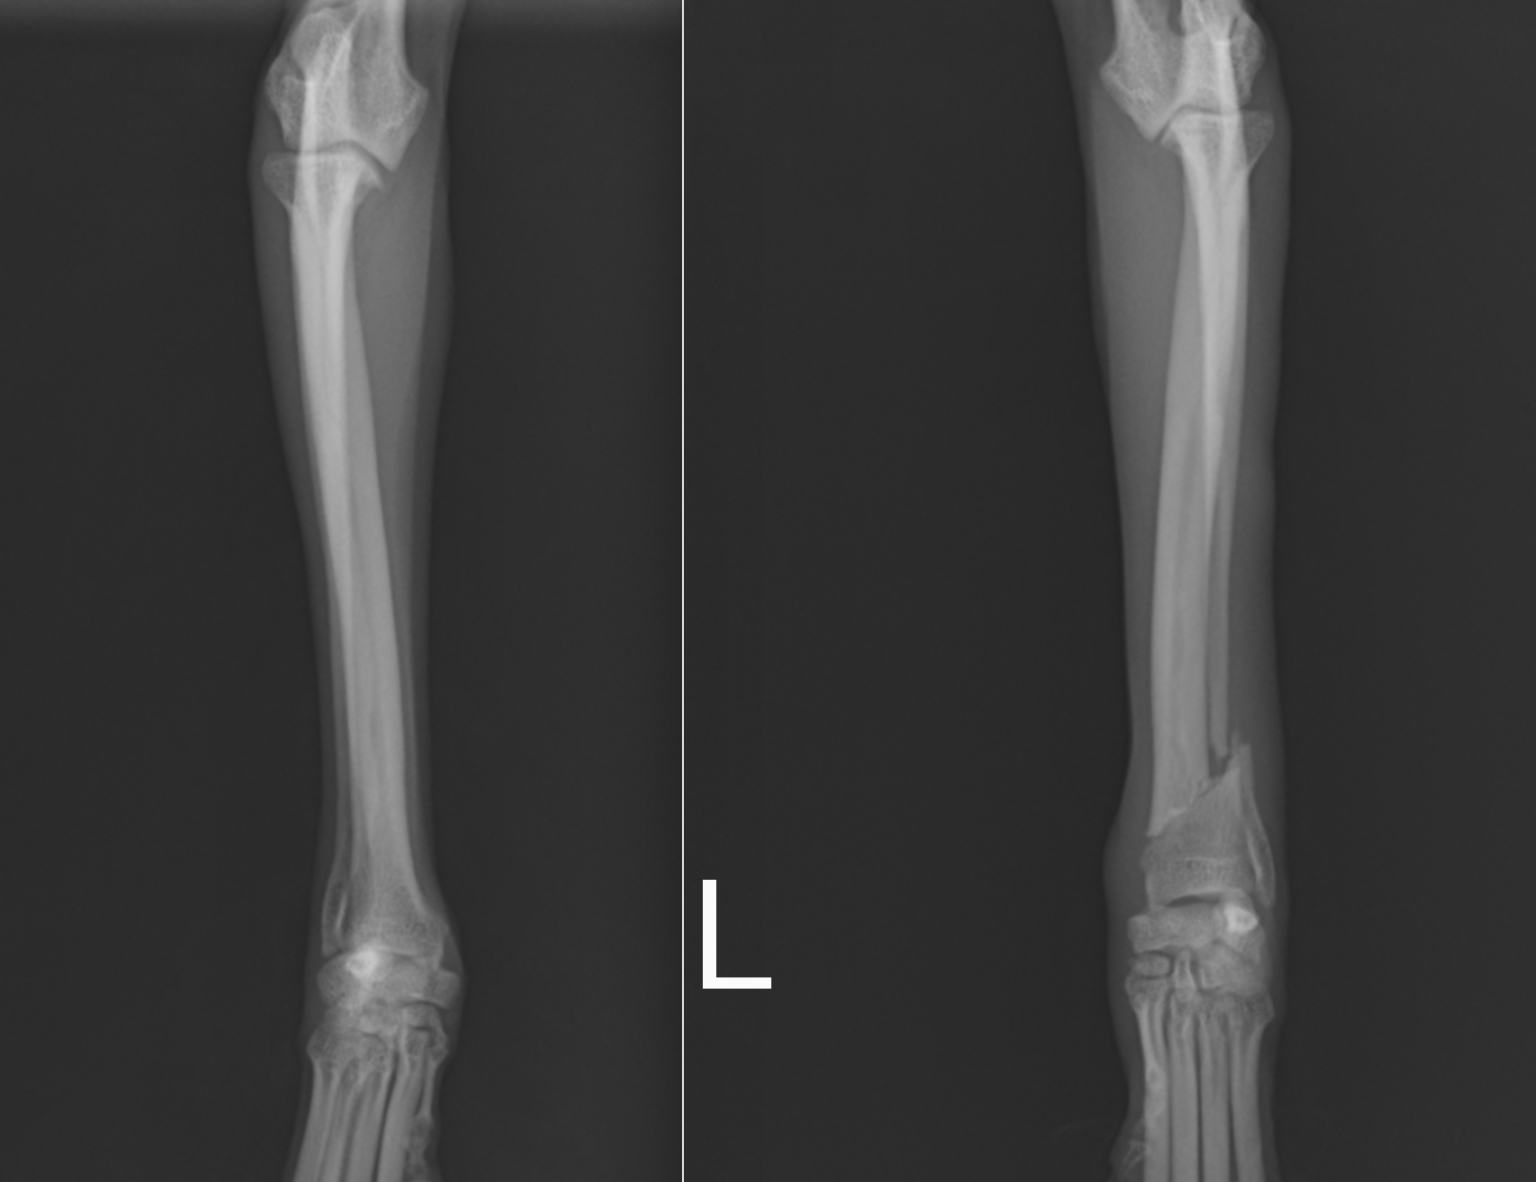

次の症例は11ヶ月のトイプードルで、スリングから飛び降りた後から足をケンケンするということで来院しました。左橈尺骨遠位斜骨折で、2日後に手術を実施しました。遠位骨折の場合尺骨(細い方の骨)には治療を行いませんが、骨折線も綺麗にあっているのがわかります。術後は次の日から足を着くことが可能で、1週間後に帰る時には通常に近い歩様で帰っていきました。その後1週間で抜糸となりますが、そこまでは散歩を5〜10分ほどにしてもらいます。ジャンプや激しい運動はしないでもらっています。その後2週間は散歩を15〜20分、その後1ヶ月は25〜30分で、その頃にプレートを1枚抜去します。

正面から見たレントゲン画像です。

横から見たレントゲン画像です。